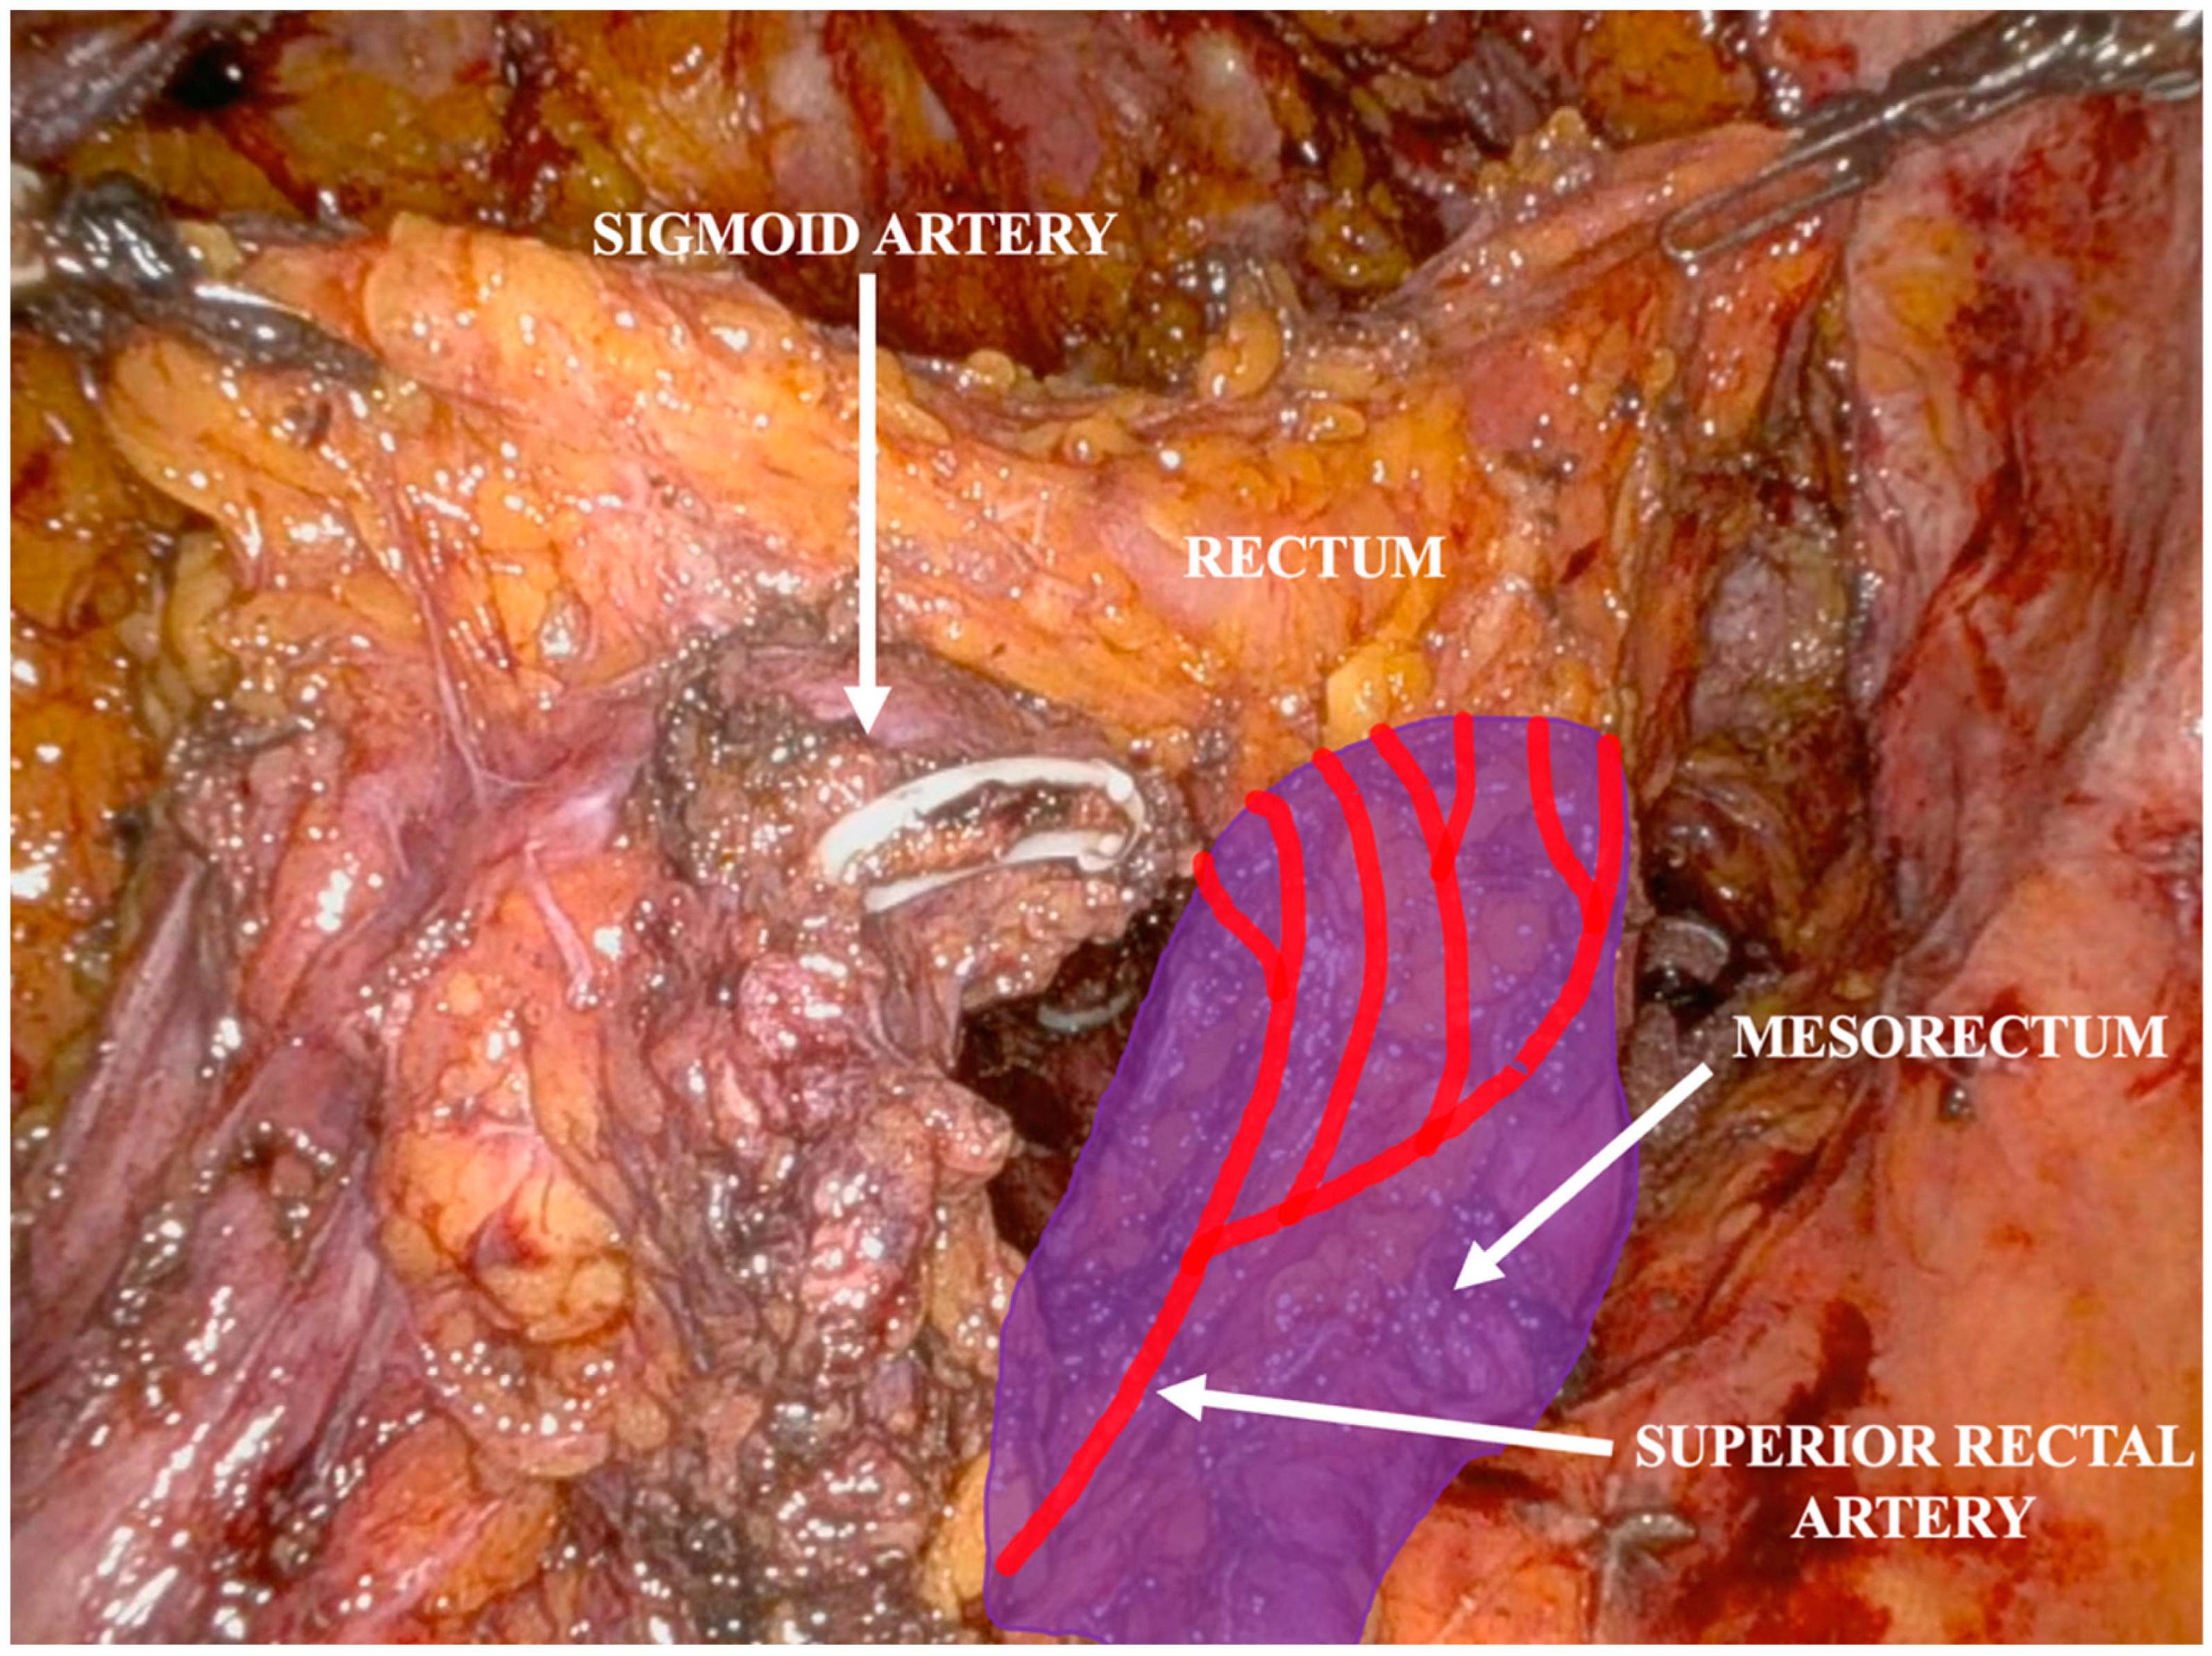

Operative Technique